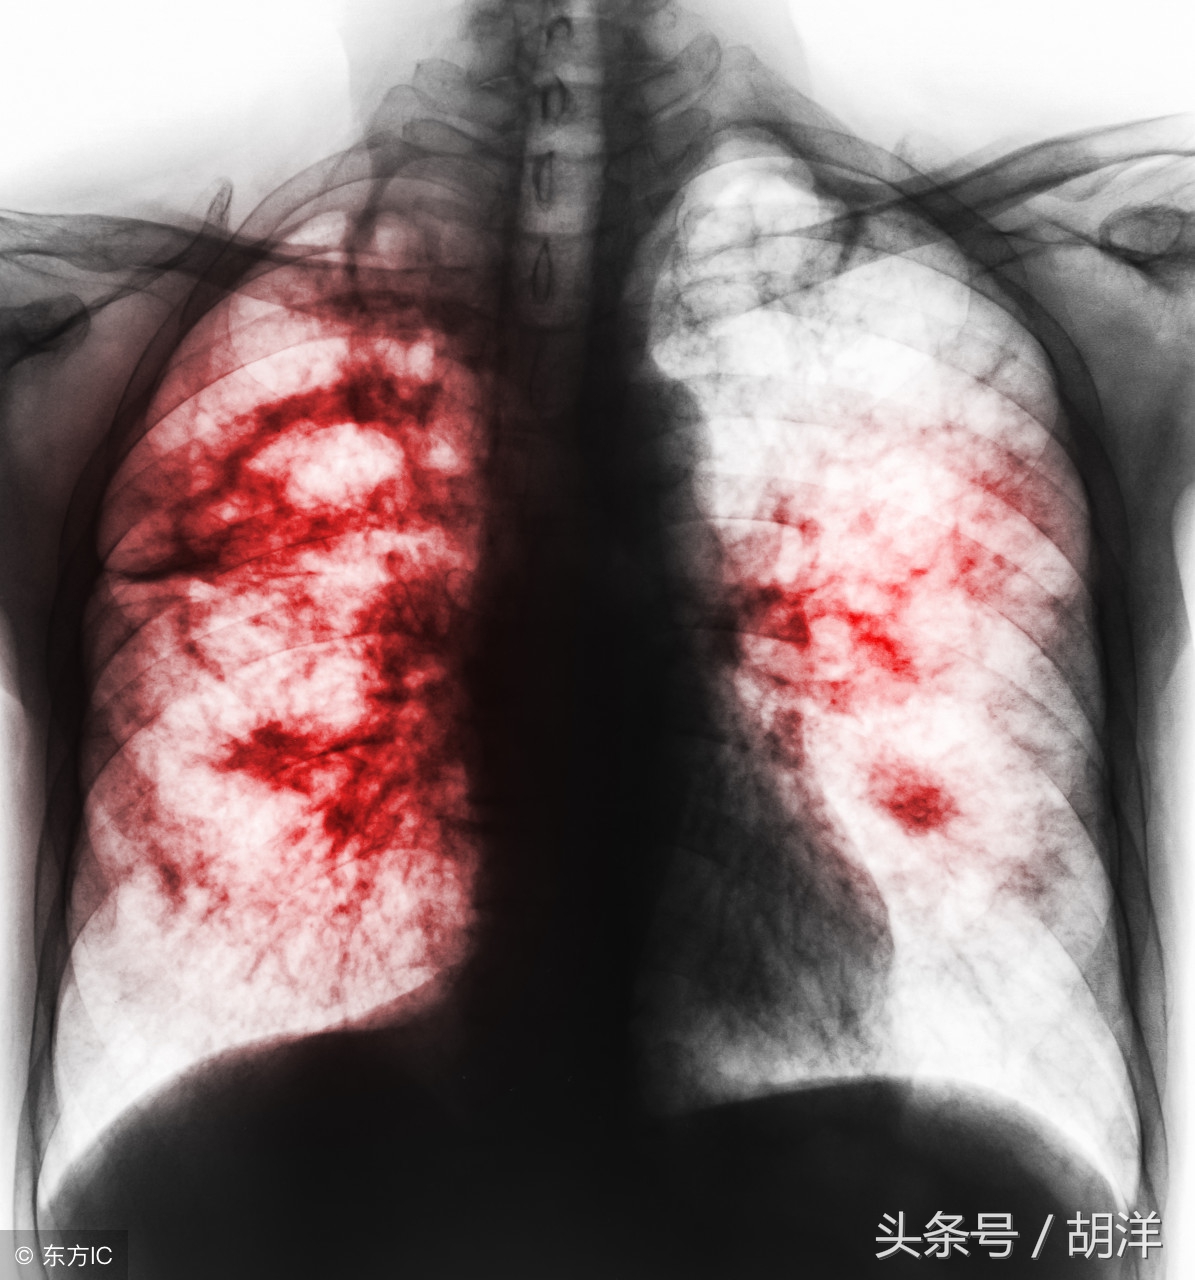

小细胞肺癌在所有肺癌病人中占15-20%,恶性程度高,容易通过血液和淋巴道转移,转移发生早而且广泛。由于小细胞肺癌与其他肺癌有完全不同的特性,因此分期方法有所不同,除了TNM分期,常用美国退伍军人分期标准,分为局限期和广泛期。局限期小细胞肺癌的特点是肿瘤局限于一侧胸腔内,包括有锁骨上或前斜角肌淋巴结转移和同侧胸腔积液。当病变超出局限期范围,均称为广泛期。

小细胞肺癌早期能发现属于比较幸运的,积极规范的治疗部分病人能达到根治的效果,能够长期生存。不过大部分病人即便早期发现,早期治疗,仍可能在2年内出现局部复发或者其他脏器转移,从局限期变成广泛期。这是因为虽然小细胞肺癌对放化疗敏感,但极易发生耐药,其癌细胞倍增时间短,短期内就会出现CT可见的复发转移病灶。